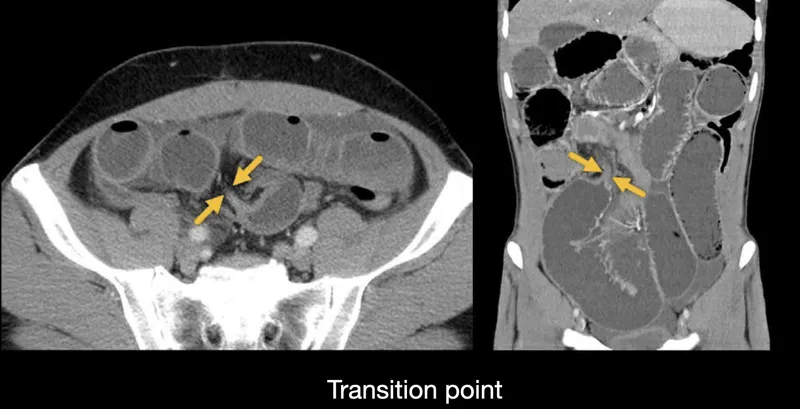

| MBO | Nausea, vomiting (bilious/feculent), abdominal distention, obstipation, colicky pain. Bowel sounds: high-pitched → absent. | Abdominal X-ray: dilated loops, air-fluid levels. CT abdomen confirms level/cause. |

- Malignant Bowel Obstruction (MBO):

- Initial: Abdominal X-ray (air-fluid levels).

- Definitive: CT abdomen/pelvis with contrast.

- Malignant bowel obstruction: Manage with NG tube decompression and consider surgical bypass or stenting.